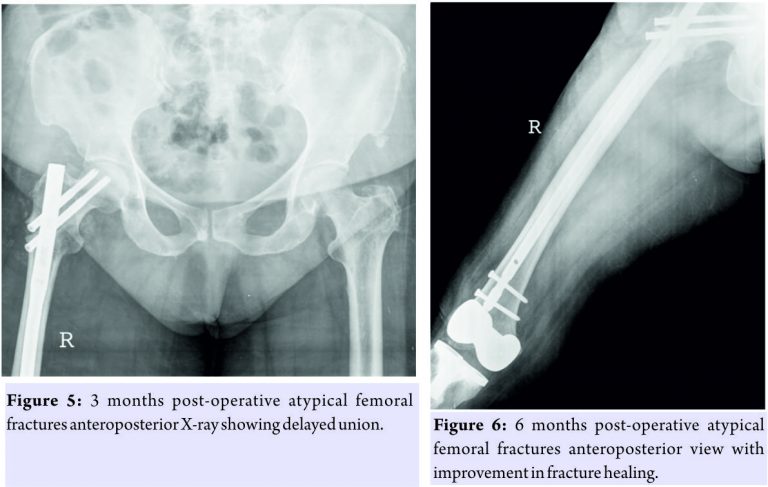

The knee replacement was unrelated to the sub-trochanteric fracture. For the subtrochanteric fracture of femur, regular follow-ups were done postoperatively with serial X-rays. Blood investigations were done, and serum calcium was 9.5mg/dl, and serum Vitamin D3 was 20ng/ml which was optimized with 6,00,000 IU of intramuscular Vitamin D3 and maintained by oral Vitamin D3 medications. At 3 months, the fracture was in delayed union (Fig. 5),and hence, the patient was started on injection Teriparatide 20mcg subcutaneous for a period of 18 months. The patient was kept non-weight bearing. The 6 months X-ray showed further progression in fracture healing (Fig. 6),and the patient was allowed partial weight bearing. In October 2013, 10 months after stopping Alendronate, she again came with the complaint of pain in the right side of the jaw; X-rays showed relapse of ONJ (Fig. 7) sequestrectomy was done on the right mandible. In February 2014, 13 months after stopping Alendronate, the patient came with the increased pain of the right mandible and was diagnosed as a fracture of the right mandible; the fracture was operated on and fixed with a plate in February 2014 (Fig.8).

Meanwhile, the patient continued injection Teriparatide. At 1year postoperatively, the atypical femoral subtrochanteric fracture had healed (Fig. 9) and the patient was allowed full weight bearing. 24 months postoperatively, X-rays confirmed solid union of the atypical subtrochanteric femoral fracture (Fig.10). On recent review, the patient walks full weight bearing without the need of any support, with a normal gait and is completely asymptomatic as regards the femur as well as the jaw.